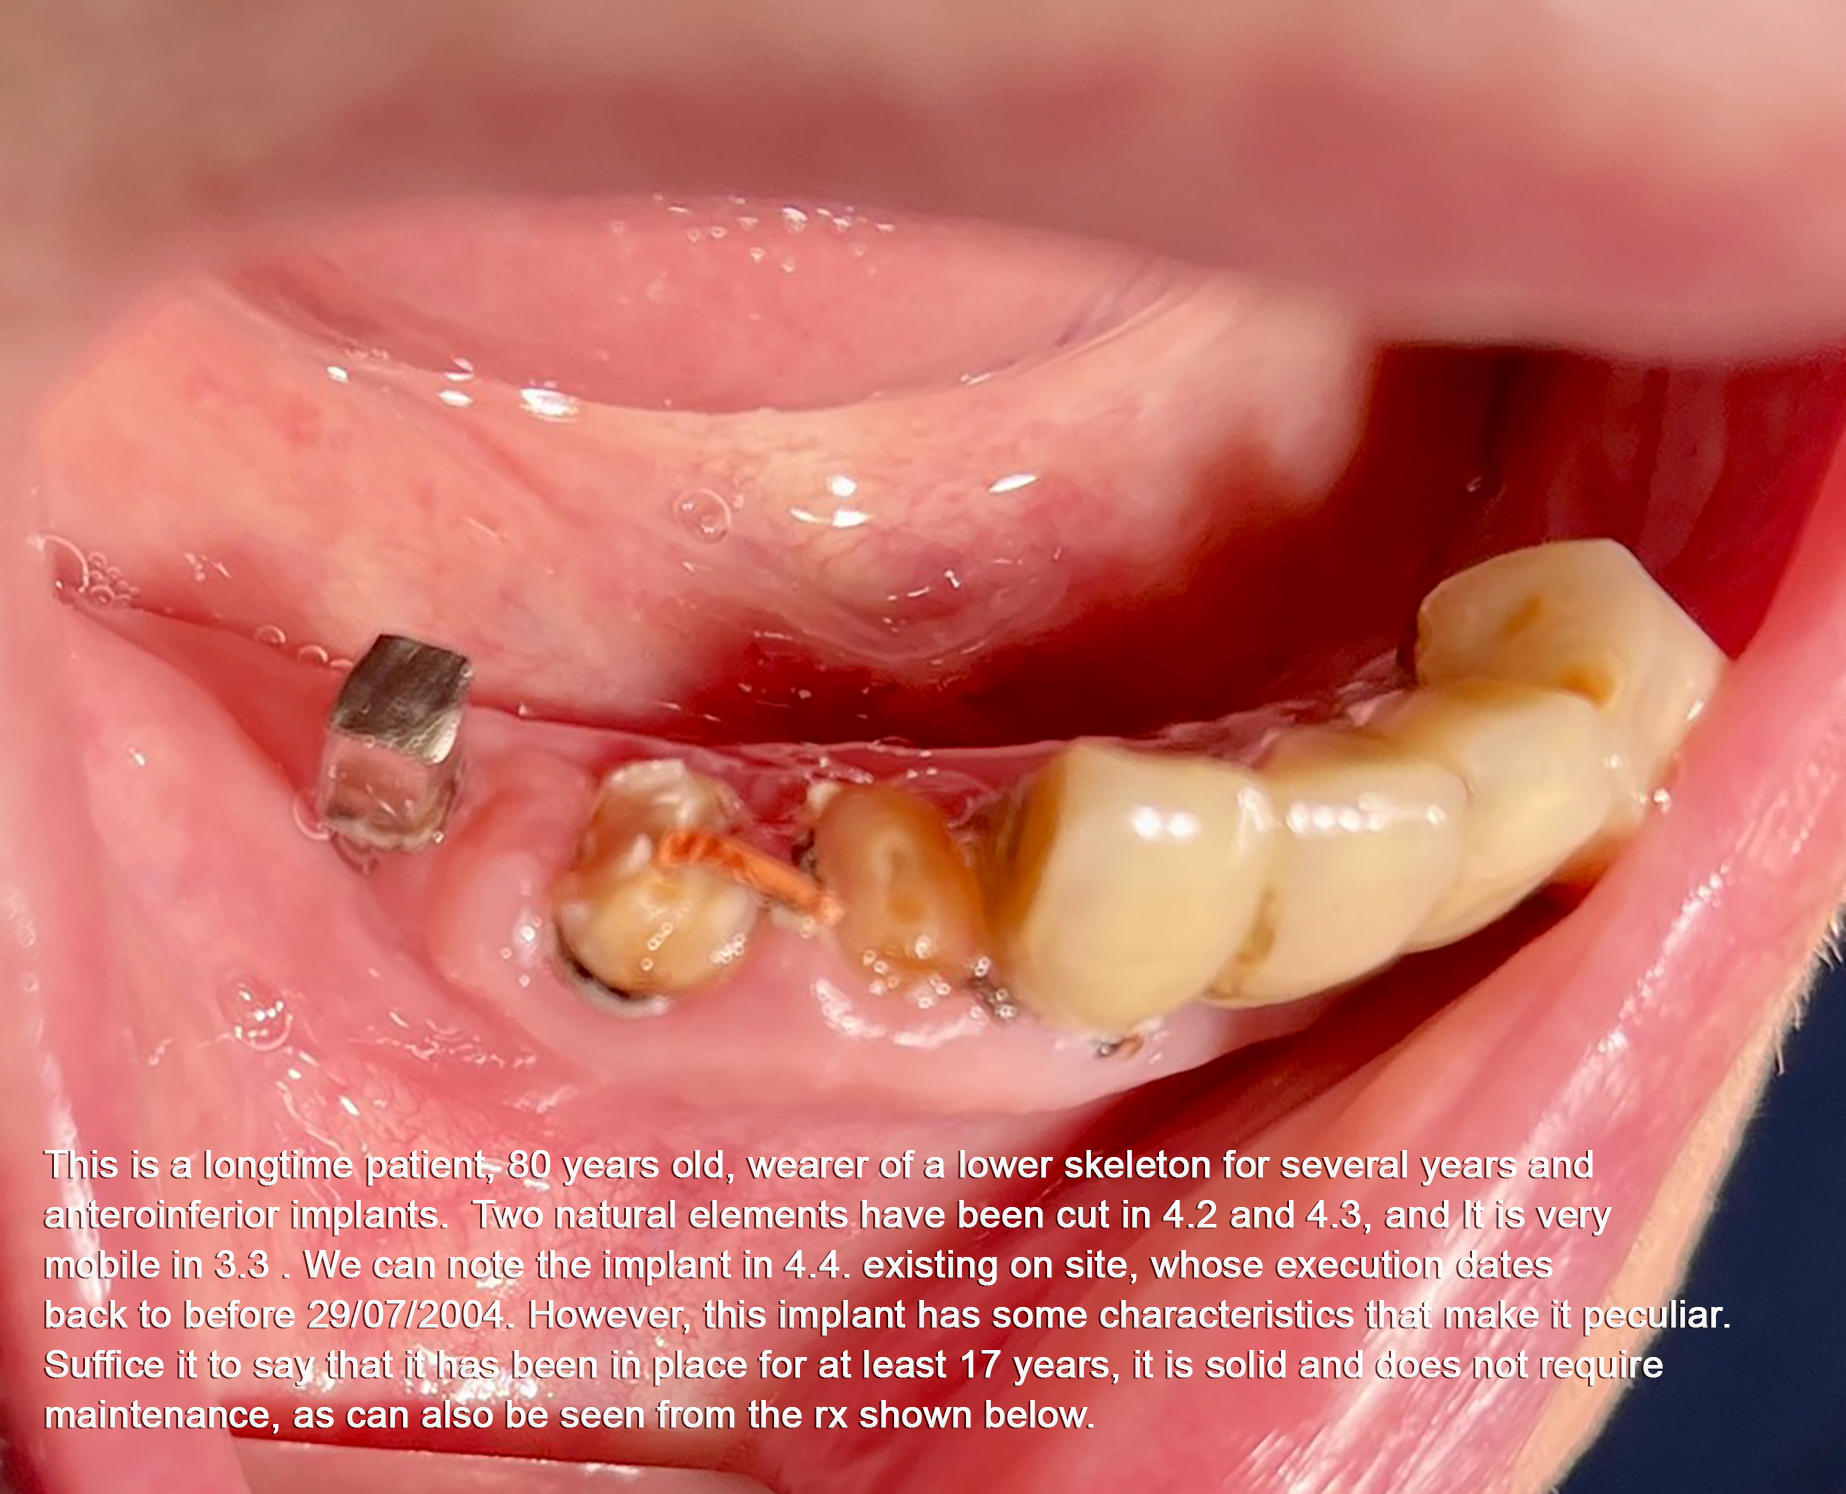

4 - TRAMONTE IMPLANT IN ADVANCED AGE

A patient with Tramonte implants for 28 years needs more implants, but is now almost 90 years old and takes a lot of medicines.